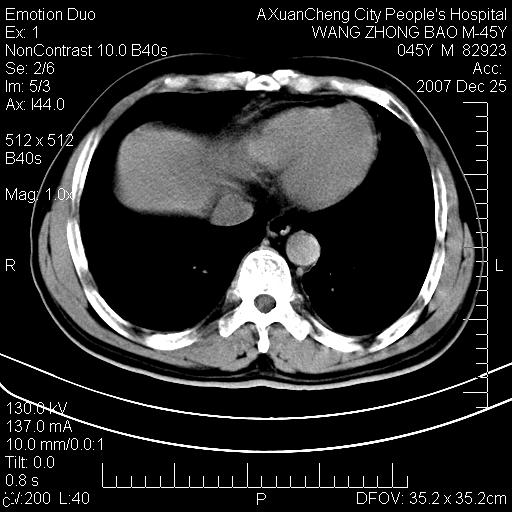

以下是引用qiuleiyu在2007-12-25 18:14:00的发言:[br]胰腺增大,周边渗出改变,肾前筋膜明显增厚,示少量积液.胆囊壁毛糙,周边少许渗出,胆总管壁厚,异常强化,然扩张不明显.结合病程急短;考虑;胆管炎,胆囊炎,胆源性胰腺炎可能大,请结合实验室检查及随访.

以下是引用lisihao在2007-12-25 14:23:00的发言:[br]急性水肿型胰腺炎[br]依据:1、胰腺弥漫性肿大,边缘稍毛糙;[br] 2、双侧肾周筋膜增厚,尤以左侧为甚(重要征象)[br] 3、双侧后胸膜增厚(刺激性炎症);[br] 4、结合病史,查血尿淀粉酶应该可以确诊。